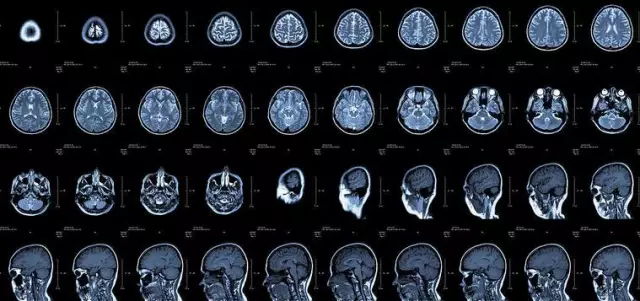

核磁共振

摇一摇再看

核磁共振机使用较强大的磁场,使人体中所有水分子磁场的磁力线方向一致,这时磁共振机的磁场突然消失,身体中水分子的磁力线方向,突然恢复到原来随意排列的状态。

简单说,就相当于用手摇一摇,让水分子振动起来,再平静下来,感受一下里面的振动。所以,核磁共振也被戏说为是摇摇看的检查。

颈椎腰椎——最佳选核磁,次选CT

颈椎病、腰椎间盘突出等椎间盘疾病需要观察椎间盘与相应的神经根,要想更好观察这些软组织,最优选择就是核磁。同样,对于关节、肌肉、脂肪组织检查,核磁也是首选。

用CT可检查冠状动脉,但冠脉CT检查辐射量较大,不适合作为常规体检。核磁虽无电磁辐射,但对冠状动脉的观察不及CT。心脏核磁则是评价心脏结构和功能的“金标准”。